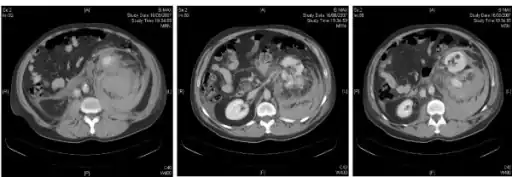

Diagnosis

Radiology

A magnetic resonance imaging (MRI) scan may be used to identify the collection of blood, although this is often not performed if bleeding is a medical emergency.[3]